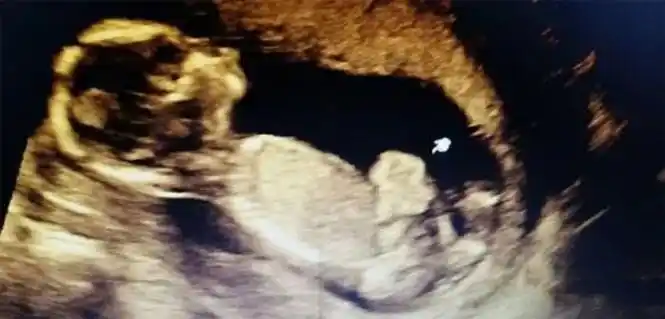

▼16周大的胎儿 小家伙用手探索自己的身体以及周围的环境

16周的b超图